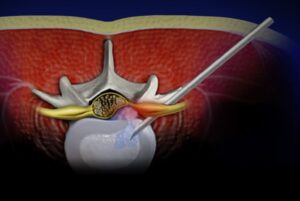

Minimally invasive treatments for spinal compression fractures, which are frequently...

Read More